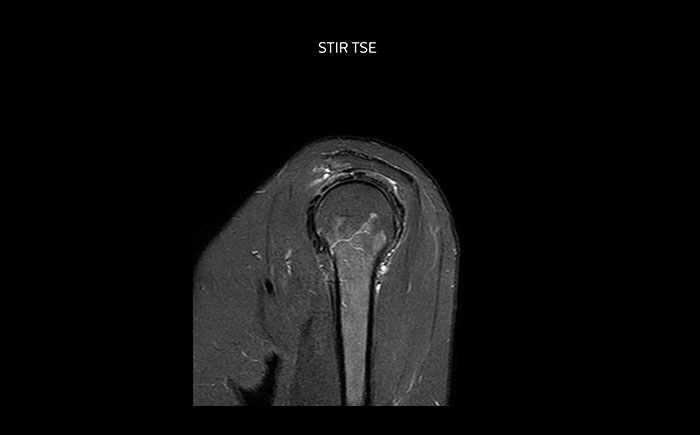

Die Prodiva Schulterspule ist sehr flexibel und hat eine grosse Abdeckung; dies erleichtert eine gute Positionierung, was wiederum zur ausgezeichneten Bildqualität und hohem SNR beiträgt, die wir in unseren Schulteruntersuchungen erreichen.

Scandauer: 2:55 Minuten, FOV: 160 mm, erfasste Voxel: 0,55 x 0,83 x 3,0 mm.

Scandauer: 04:19 Minuten, FOV: 160 mm, erfasste Voxel: 0,55 x 0,80 x 3,0 mm.

Scandauer: 02:50 Minuten, FOV: 160 mm, erfasste Voxel: 0,70 x 0,99 x 3,0 mm.